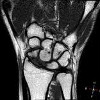

КТ лучезапястного сустава

КТ лучезапястного сустава назначают пациентам для диагностики травматических повреждений. Во время сканирования могут быть обнаружены переломы костей запястья, дистальной лучевой и локтевой костей, переломы запястья и вывихи костей запястья. Кроме того, с помощью исследования можно определить давние посттравматические изменения в костном и хрящевом аппарате. Томография показана при подозрении на синдром запястного канала. Методика эффективна при диагностике воспалительных процессов - артрита, остеомиелита. Используя компьютерную томографию, можно оценить обширность патологического очага и распространенность изменений в окружающей ткани. Кроме того, этот метод используется для обнаружения гноя, крови в суставной полости.

КТ является информативным для определения доброкачественных и злокачественных опухолей. Получение послойных изображений позволяет диагностировать новообразования небольшого размера, не сопровождающиеся клиническими проявлениями, выявлять метастазы. Сканирование используется для выявления дегенеративно-дистрофических изменений, в частности артроза, остеопороза. Показанием для исследования является подозрение на врожденные или приобретенные аномалии структуры сустава. В качестве дополнительного диагностического метода рентгеновский метод используется при ревматологических заболеваниях, системных поражениях соединительной ткани, при подготовке к операции или для контроля эффективности хирургического вмешательства.

КТ лучезапястного сустава похожа по своей эффективности на МРТ, но последняя предполагает использование магнитного поля и радиоволн. С помощью компьютерного сканирования можно визуализировать элементы кости как можно более подробно, в то время как магнитно-резонансная томография предоставляет исчерпывающую информацию о состоянии мягких тканей. Еще одним преимуществом МРТ является отсутствие рентгеновского облучения. Тем не менее, КТ является более доступным с точки зрения стоимости, поэтому он используется гораздо чаще. Процедура может быть назначена даже в детстве, если есть трудности в диагностике.